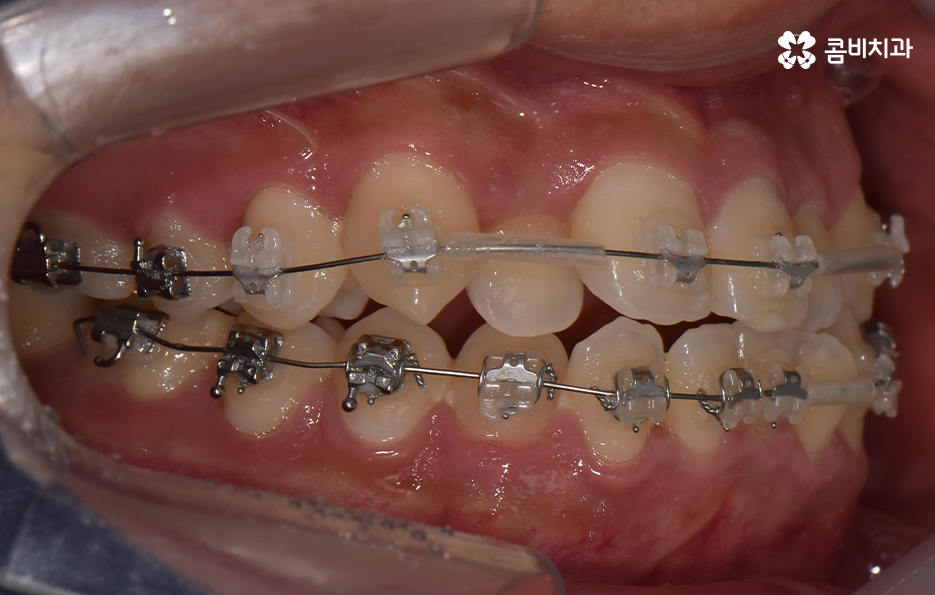

오늘 포스팅에서 보여지는 사진에서는 비발치 교정으로 덧니 교정이 가능했던 사례입니다. 덧니 교정 사례에서 발치교정 케이스는 흔한 치료 방법이긴 하지만 발치에 대한 판단은 치열만이 아니라 골격과 얼굴형을 종합적으로 고려하여 판단하고 치아를 얼마나 이동시켜야 할지 예측하여 판단하기 때문에 3D CT 등의 첨단 장비를 통한 검진과 경험 많은 교정 전문의와 충분히 상의하고 결정해야 합니다

종합하면 발치교정의 필요성은 얼굴과의 조화, 골격 그리고 교합 등을 전체적으로 고려하여 판단하기 때문에 각 환자분들이 필요한 치아의 이동 정도를 정확히 예측하고 필요한 치아 이동 공간을 확보함에 있어서 발치교정이 적합할지 아니면 비발치적인 방법으로도 치아 이동 공간이 확보 가능한지 따져보고 있으며 발치교정이 아니더라도 치간삭제, 악궁확장, 어금니 후방이동과 같은 방법으로 공간 확보가 가능하기 때문에 각 환자분들에게 적합한 1:1 맞춤형 치료가 진행되고 있어요